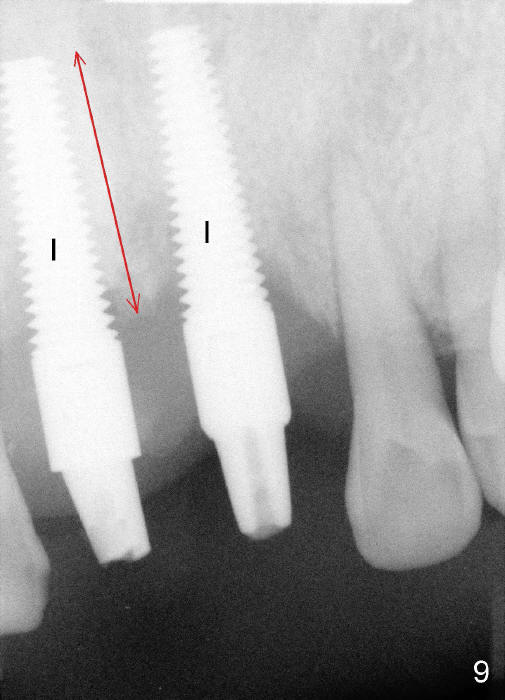

In fact two of 4.5x20 mm implants are placed immediately following extraction. Insertion torque is greater than 60 Ncm, partially because of apparent engagement of the implants into the nasal floor (cortical bone; Fig.9). Following placement of 3.5x5 mm abutments, immediate provisionals are fabricated (Fig.7,8).